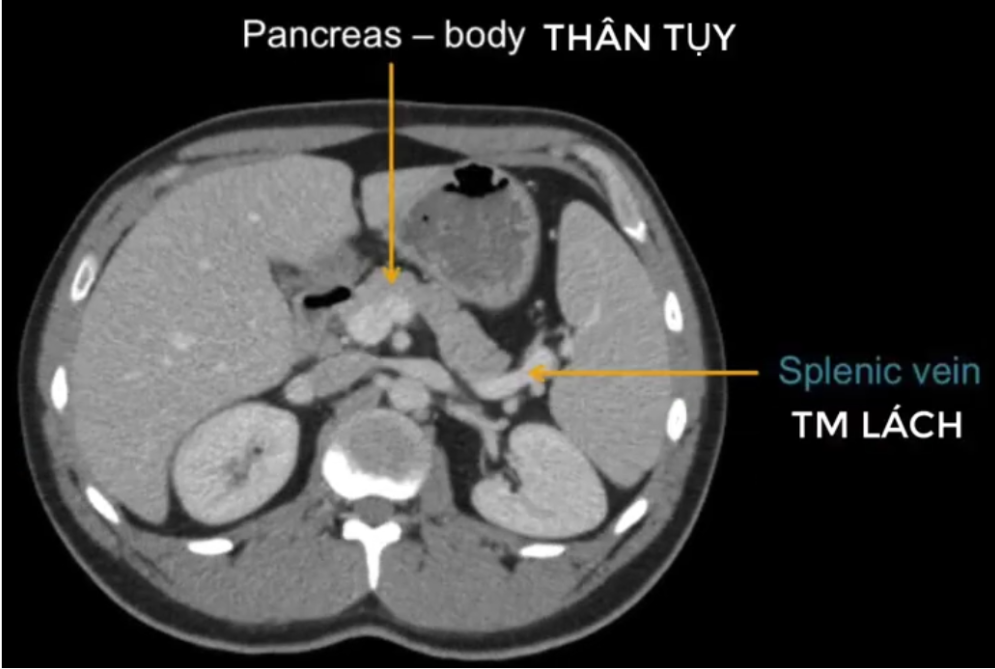

cq trong hình ?